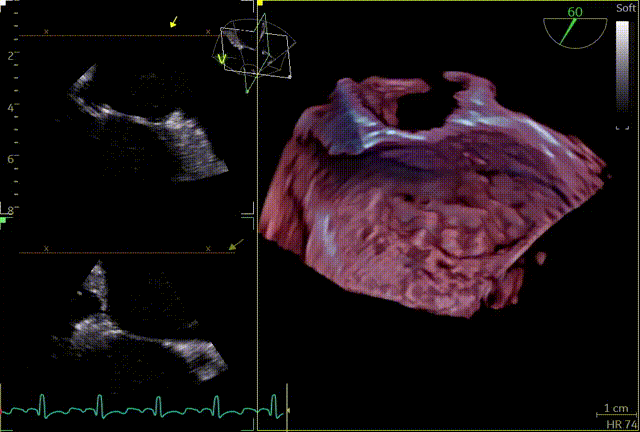

俞飞成教授认为从术前超声来看,该患者反流束非常宽,至少需要2枚夹子,2区及3区后叶栓系,有明显gap,3区gap较大,捕捞夹持有难度;左房较大,心脏转位,图像挑战,穿刺挑战大,是一个高难度的Case。术者团队考虑2区优先G4 XTW夹持,改善对合,内侧根据剩余反流情况再补夹子,夹子型号待定,外侧根据剩余反流情况决定是否需要再补夹子。

术中操作

患者全麻,全身覆盖消毒铺巾后,在超声引导下建立右侧股静脉入路,在食道超声引导下,穿刺房间隔,术前左房压较高,平均32mmHg,且心脏转位,穿刺针下拉过程中难以在卵圆窝中部定位,往后转穿刺针滑脱,在靠下的位置穿刺通过,位置太低,重新穿刺,滑脱2次后,下腔靠近肌部产生血肿,最终成功穿刺,穿刺高度4.0cm,SGC置入后,3D复测穿刺高度为3.8cm,然后将二尖瓣夹输送系统XTW送入左心房,到达二尖瓣目标位置,调整二尖瓣夹轨迹和方向,使其垂直于二尖瓣环平面且指向心尖,完成左房初定位,夹臂方向指向12点-6点方向,在瓣上充分释放张力。

第一次房间隔穿刺

房间隔血肿

第二次房间隔穿刺

3D辅助辅助观察点位

穿刺高度

3D复测穿刺高度

第一个夹子XTW

关小夹子,进入到左室后,跨瓣越过瓣叶尖端后,立马打开夹子,三维再次确认夹臂方向未改变,慢慢往上提拉,一次准确捕获瓣叶,前后叶Bouncing明显,后叶接近根部,关紧夹臂,反流量整体减少,但是内外侧都残余反流,内侧为主。反流明显减少,后叶夹持10mm以上,夹子稳定性良好,跨瓣压差小于3mmHg,决定释放。

释放前评估

释放后